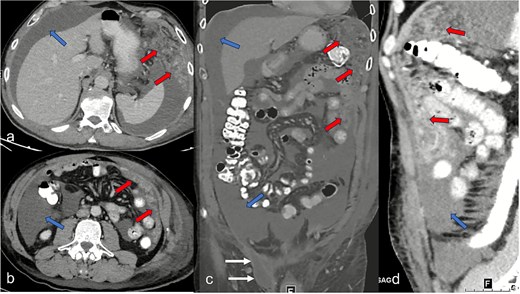

A 52-year-old male patient presented for surgical treatment of a recurrent hernia in the right groin. The preoperative sonography revealed a hernial orifice with a diameter of ~1 cm. In addition, there was clear ascites with a collection of fluid in the spermatic funiculus and a suspected mural tunica vaginalis. A subsequent magnetic resonance imaging (MRI) examination of the pelvis showed a similar picture (Fig. 1). Due to the suspicious appearance of the tunica vaginalis, the recurrent hernia was not repaired at that time. In the renewed physical examination and history taking, the patient reported not only the familiar painful feeling of pressure in the area of the known inguinal hernia but also an increasing feeling of fullness over the entire abdomen. He had also lost 3 kg in weight in the last two months. He had been professionally exposed to asbestos while working as a master electrician in old houses. In the blood count, the C-reactive protein was slightly elevated at 1.88 mg/dl, the thrombocytes at 456 000/μl and the leukocytes at 12 000/μl. The subsequent computed tomography (CT) thorax and abdomen revealed a peritoneal carcinomatosis with ascites without evidence of a primary tumor (Fig. 2). An ascites puncture with subsequent cytological analysis revealed no pathological findings. The subsequent diagnostic laparoscopy revealed a four-quadrant metastasis with nodular structures on the peritoneum (Fig. 3) and the greater omentum. Biopsies taken from the peritoneum and greater omentum revealed a malignant high-grade epithelioid mesothelioma of the peritoneum (Fig. 4). After the tumor conference decision, another laparoscopy was performed to reduce the tumor tissue, after which the affected greater omentum and part of the peritoneum were removed. Hyperthermic intraperitoneal chemotherapy (HIPEC) was then carried out, which was well tolerated and led to a complete remission during the 24-month follow-up period.

Diagnostic laparoscopy. The image shows the nodularly altered peritoneum.